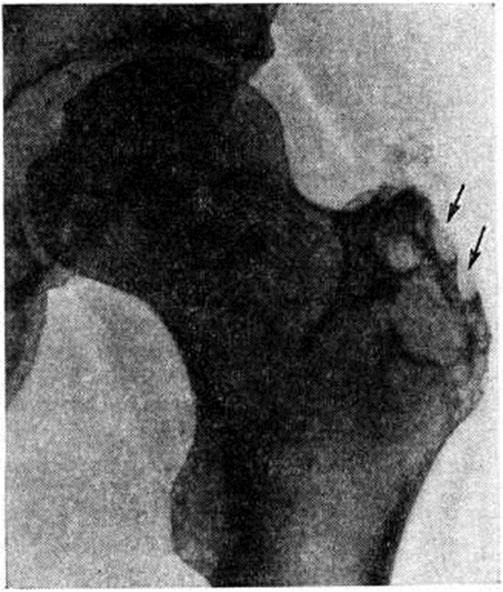

Туберкулёзный очаг вначале располагается в толще большого вертела, чаще у его наружной поверхности (рисунок), поэтому воспаление быстро распространяется в мягкие ткани и осложняется натечным абсцессом (смотри полный свод знаний: Натечник) или свищом. Свищи (смотри полный свод знаний) обычно короткие, прямые, но могут распространяться вдоль мышц бедра, становясь извилистыми и длинными, открываясь на задней и боковой поверхностях бедра. В таких случаях показано рентгеноконтрастное исследование — абсцессография (смотри полный свод знаний) и фистулография (смотри полный свод знаний). При этом может быть установлена связь мягкотканного воспалительного очага с первичным костным очагом, выявлена разветвленная сеть свищевых ходов, наличие затеков. Очаг деструкции в большом вертеле обычно имеет размеры от 4—5 миллиметров до нескольких сантиметров в диаметре, контуры его неровные, нечеткие, кость вокруг очага порозна, если нет свищей. Свищевые формы обычно осложняются вторичной инфекцией, что приводит к образованию зоны диффузного остеосклероза вокруг очага деструкции. Постепенно деструктивные изменения нарастают, процесс распространяется как в глубь большого вертела, так и по поверхности, в краевых отделах появляются секвестры диаметром не более 1 сантиметров, имеющие, как правило, большую плотность по сравнению с сохраненной костной тканью.